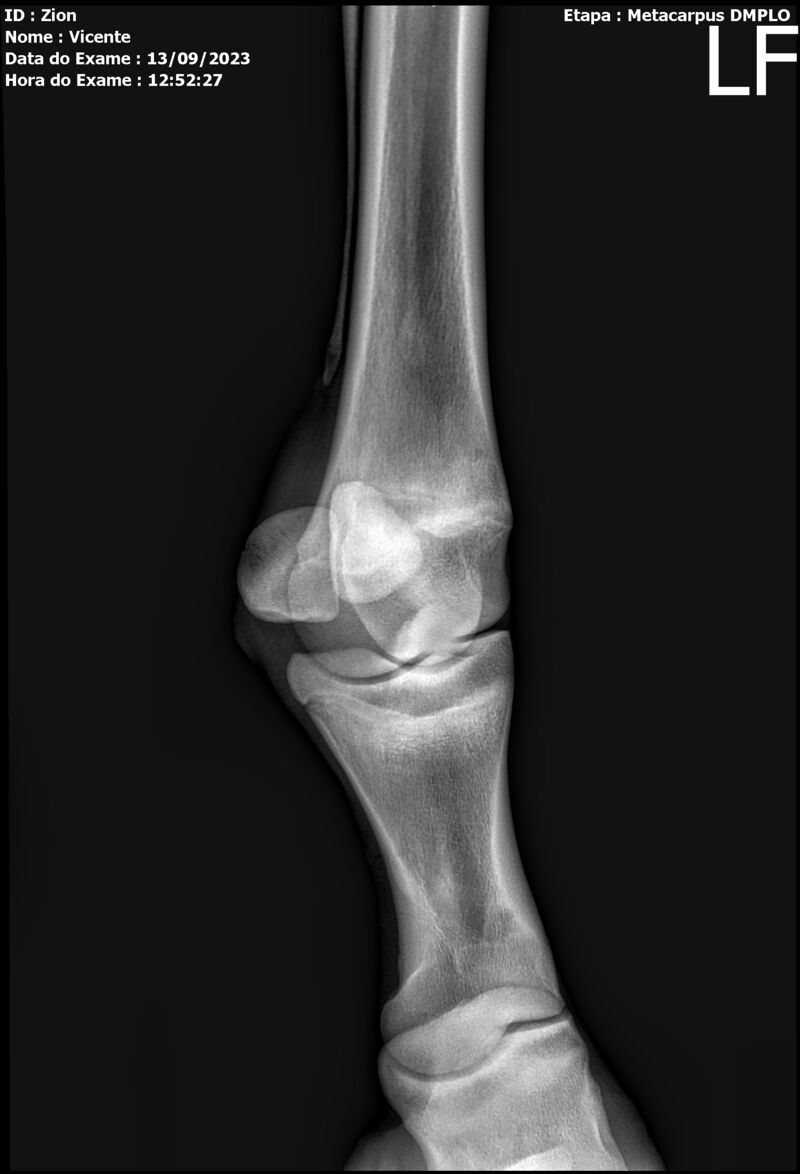

ZION ZC

Raça: BRASILEIRO DE HIPISMO

Sexo: MACHO - POTRO

Nascimento: 17/12/2022

Altura Aproximada: 1,51

Pel.: CASTANHO

Registro: EM AND

Vend.: VICENTE CONTE

Local : PORTO FELIZ/SP